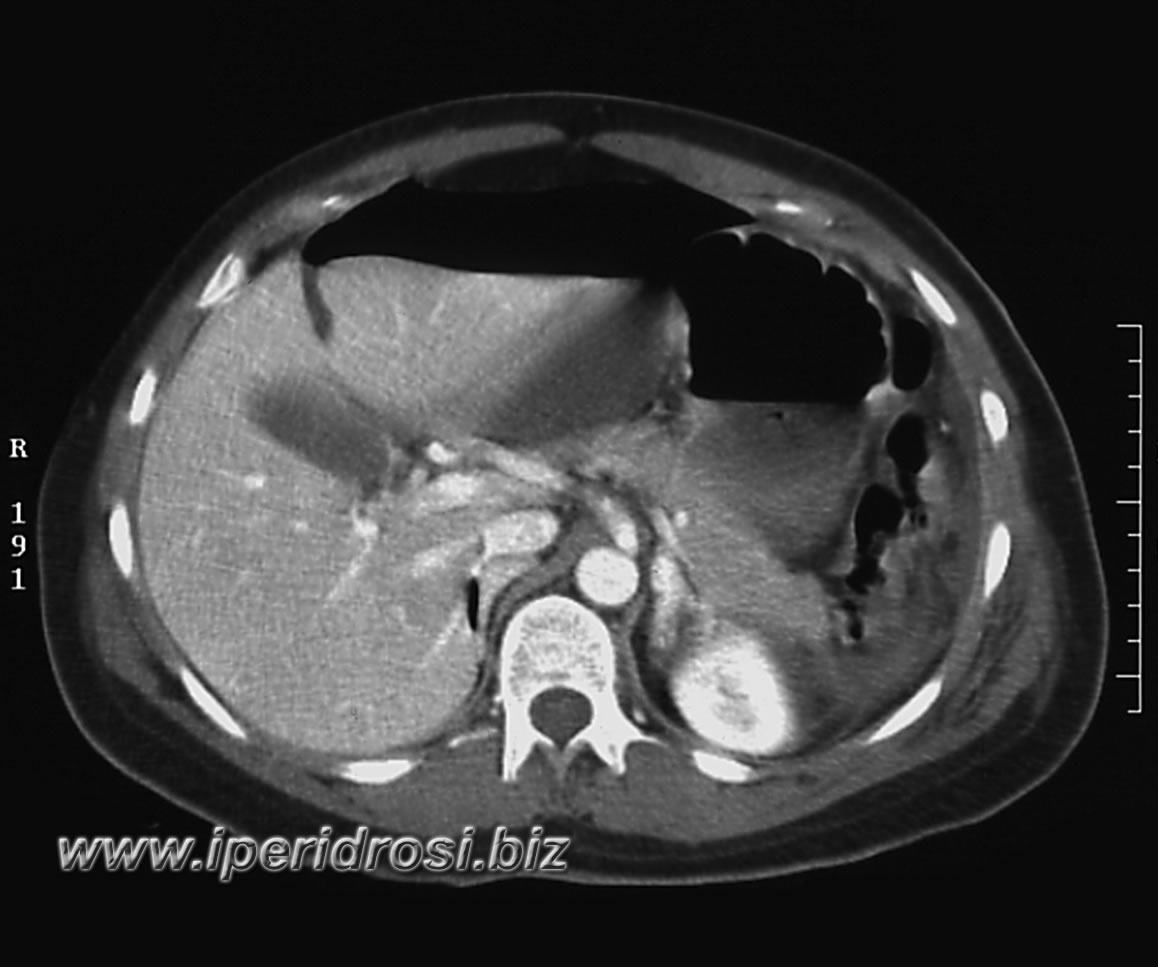

Torace: a sinistra abbondante versamento pleurico e parzialmente saccato, atelettasia parenchimale basale bilaterale più evidente a sinistra dove residua limitato parenchima ventilato.

Addome: abbondante versamento addomino-pelvico diffuso con falda aerea piuttosto abbondante all'addome superiore. Rene a ferro di cavallo con cisti parapieliche a sinistra. Distensione del colon da meteorismo ed ispessimento delle pareti intestinali con iperemia di numerose anse.